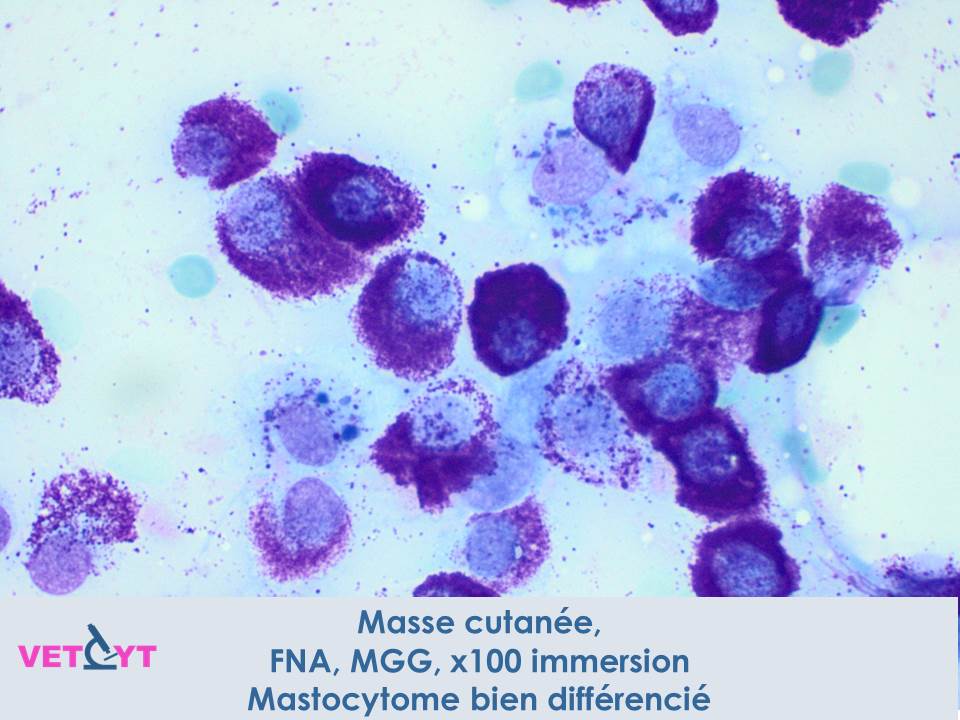

1) Le mastocytome est une tumeur à cellules rondes qui se reconnaît en cytologie par ses granules mauves caractéristiques.

3) Le mastocytome est souvent accompagné d’une infiltration éosinophilique, et parfois de fibroblastes et de collagène.

4) Les granules peuvent ne pas se colorer avec les kits de coloration rapide type hemacolor® ou diff-quick® avec potentielle erreur diagnostique à la clé. Préférez une coloration de May-Grunwald-Giemsa ou au bleu de toluidine quand un mastocytome est suspecté.

6) Un aspect cytologique bien différencié et monomorphe n’exclut pas un fort potentiel métastatique. A l'inverse, un aspect peu différencié avec des critères de malignité évidents permettent de suspecter un haut grade.